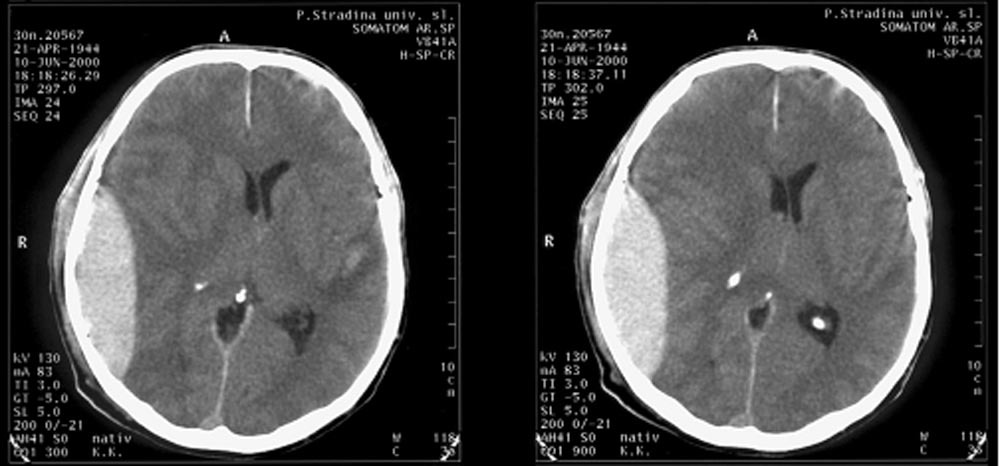

Субдуральная гематома диагностика